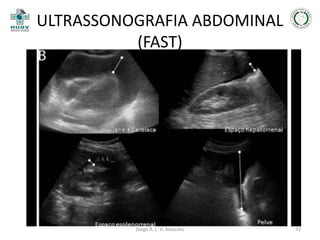

ULTRASSONOGRAFIA ABDOMINAL

(FAST)

• Objetivo;

• Sensibilidade está entre 80 a 99%;

• Vantagens;

• Desvantagens.

JAYANTHI, 2011

Diego R. L. H. Mascato

30

31

32